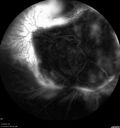

Siegrist Streaks and severe diabetic macular edema141 views56 year old female who presents four years after developing necrotizing fascitis and multiple organ failure from an infected foot from a roofing nail. Her vision was 20/100 OU. She has multiple peripheral pigment spots consistent with Siegrist streaks.Sep 19, 2023